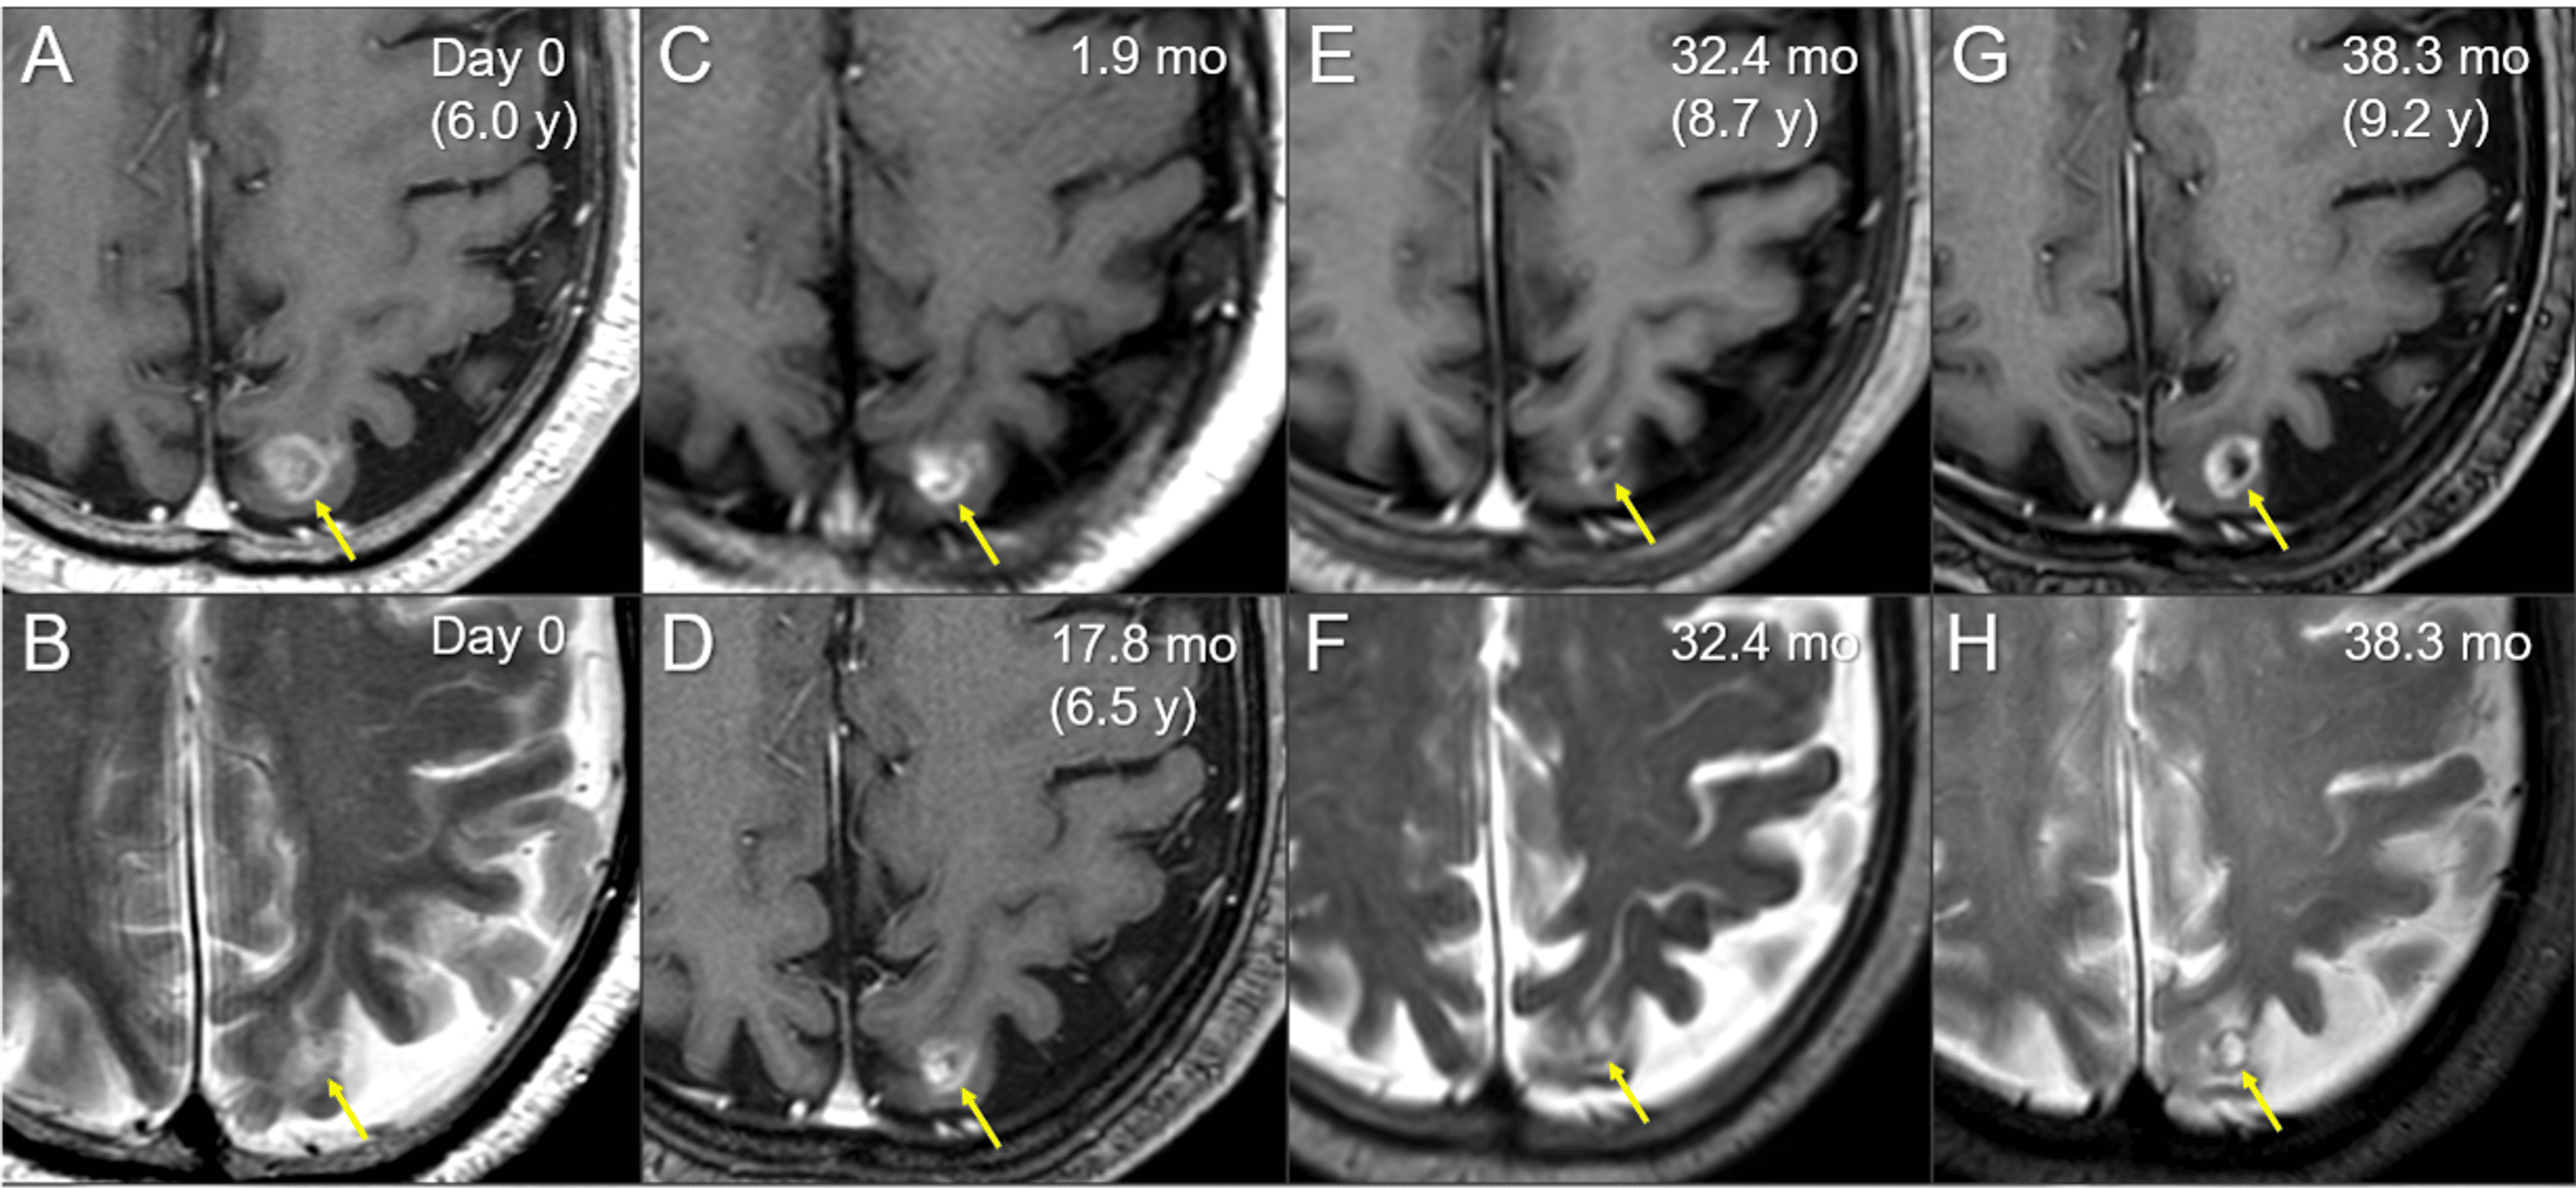

Cureus FiveYear Sustained Complete Remission With Minimal Adverse Radiosurgery Protons For many patients, stereotactic radiosurgery (srs) offers a minimally invasive, curative option when surgical techniques are not. Web in preparing to use protons in radiosurgery and radiotherapy, radiobiological effects of protons were studied extensively by. Web despite requiring specialized facilities for its generation and manipulation, proton radiation offers superior dose conformality relative. Part i deals with the relevant physics and. Radiosurgery Protons.